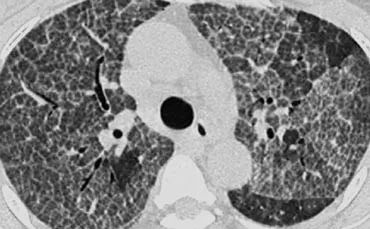

下图HP,GGO呈马赛克分布。

一些小叶受累,而另一些则没有。

鉴别诊断为过敏性肺炎、毛细支气管炎或血栓栓塞病。

过敏性肺炎通常表现为磨玻璃密度的小叶中心结节(腺泡结节)。

当它们汇合时,HRCT显示弥散的GGO。

过敏性肺炎(HP)是一种由吸入各种有机粉尘中所含抗原引起的过敏性肺病。

HP通常以两种形式出现,一种是镶嵌分布的GGO,如本例;另一种是磨玻璃密度的小叶中心结节(腺泡结节)。